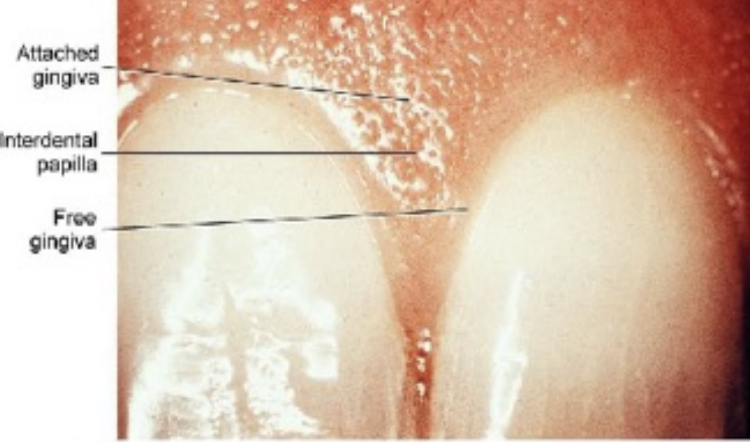

Oral mucosa

The oral mucosa is used to describe the moist lining of the oral cavity, it is made of an epithelium and connective tissue. It can be classified into: lining mucosa, masticatory mucosa, and specialized mucosa, with distinctive histological, clinical, and functional features.

The gingiva and hard palate are a part of masticatory mucosa, masticatory mucosa also bears the forces of mastication and is usually keratinized and 25% of the total mucosa

Dentogingival junction is the region where the oral mucosa meets the surface of the tooth. Very important because it is a weak area in the oral mucosa.